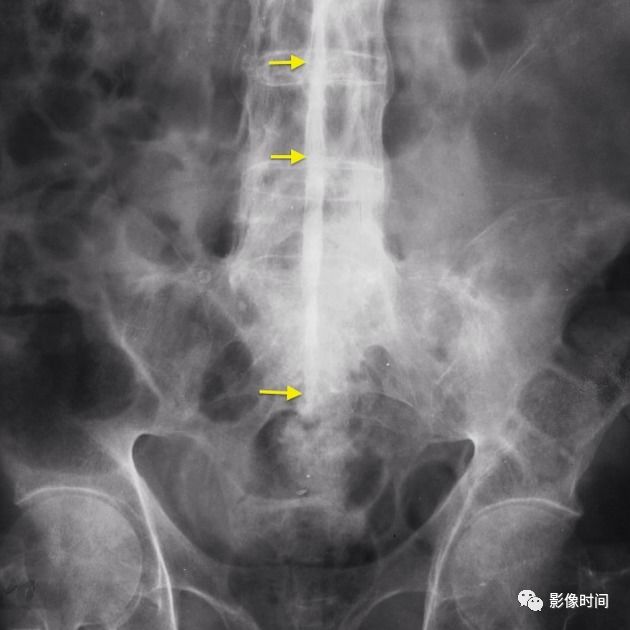

19竹节椎

竹节椎(Bamboo spine)

竹节椎是用于描述强直性脊柱炎的一个放射学特征,由于椎旁韧带广泛骨化,导致椎体融合强直,这种薄而连续的韧带骨化在正位片使得脊柱的轮廓呈现波浪起伏状,宛如具有多个竹节的一根竹竿,故而得名。

典型病例

强直性脊柱炎。腰椎正位片示腰椎韧带、小关节囊广泛骨化,骨性强直,呈典型竹节椎表现。另可见骶髂关节骨性融合。

20匕首征

匕首征,或译为短剑征(Dagger sign)

匕首征是指由于棘间韧带骨化,导致在正位 X 线片上呈现垂直的一条硬化带(白箭),形似一把短而窄的匕首而得名。此征象也主要用于描述强直性脊柱炎。

强直性脊柱炎。正位 X 线片示棘间及棘上韧带骨化形成匕首征(黄箭)。另可见双侧骶髂关节骨性融合,双髋关节间隙均匀性狭窄。

21

电车轨道征

电车轨道征(trolley-track sign)

电车轨道征是指在正位 X 线片上,强直性脊柱炎患者由于棘上及棘间韧带骨化,两侧小关节囊骨化强直,形成竖向排列的三条高密度线,类似无轨电车的轨道,故而得名。

63 岁女性,强直性脊柱炎。正位 X 线片示由于棘上及棘间韧带骨化以及关节突关节强直,呈现电车轨道征。